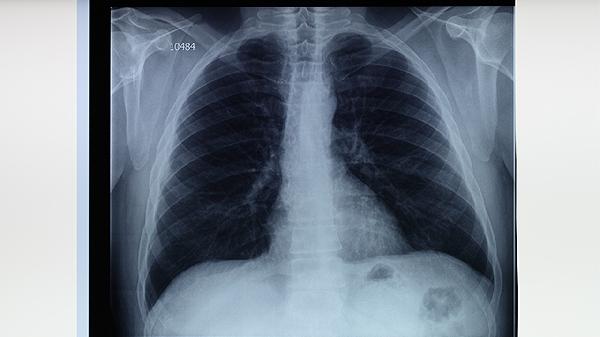

肺結(jié)核的中醫(yī)治療方法主要有中藥湯劑調(diào)理、穴位敷貼、針灸療法、食療輔助以及氣功導(dǎo)引等。肺結(jié)核在中醫(yī)稱為肺癆,多因正氣不足、癆蟲侵襲所致,需結(jié)合辨證施治原則干預(yù)。